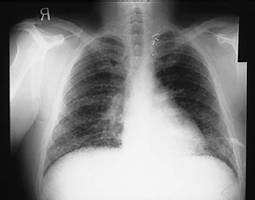

A 34-year-old amateur spelunker develops cough, dyspnea, and fever 2 weeks after a caving expedition to caves in Kentucky. On physical examination, the patient's temperature is 102°F and respiratory rate is 24. On pulmonary examination, there are diffuse crackles bilaterally. A CXR is shown in Figure

.

The patient has diffuse interstitial infiltrates on CXR that correspond in time and presentation to acute inhalation histoplasmosis. This would be seen in a patient, such as an amateur spelunker, who has been in a cave with bats. It is the act of crawling through the cave that disturbs the spores of histoplasmosis that grow in the bat guano. The incubation period for influenza is 12 days. It is passed primarily by secretions from the nose spread by hands. The other members of the expedition were not sick, as they might be with influenza. Disseminated aspergillosis occurs in immunocompromised patients who have defects in both cell-mediated and humoral immunity. This patient does not have this. While the CXR could mimic military tuberculosis, the association with caving 14 days before would make tuberculosis less likely and histoplasmosis more likely. There is no history that the patient is immunocompromised with HIV and would be at risk for P. jiroveci pneumonia. Fungal serologies would establish the diagnosis, but acute and convalescent serologies would take 3 weeks for results. These are only useful in outbreak investigations. The other choices do not fit due to the reasons above. Treatment of acute respiratory histoplasmosis is based on severe hypoxia and would require arterial blood gases to establish the need for therapy. None of the fungal infections mentioned are transmissible person to person, therefore respiratory isolation would not be necessary. Histoplasmosis is a dimorphic fungus that grows as a yeast at body temperature and a mold at room temperature. The mold produces the spores that are infectious. A similar situation occurs for Cryptococcus neoformans. C. immitis and aspergillosis are not transmitted from person to person.